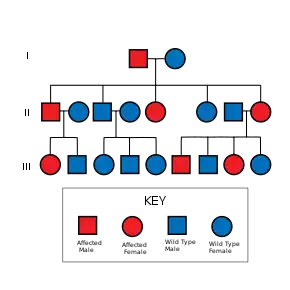

NF2 is an inheritable disorder with an autosomal dominant mode of transmission.[4]

NF2 is caused by inactivating mutations in the NF2 gene located at 22q12.2 of chromosome 22, type of mutations vary and include protein-truncating alterations (frameshift deletions/insertions and nonsense mutations), splice-site mutations, missense mutations and others. Deletions, too, in the NH2-terminal domain of merlin proteins have been associated with early tumor onset and poor prognosis in people with NF2.[6] Protein truncating mutations correlate with more severe phenotype.[7] There is a broad clinical spectrum known, but all people with the condition who have been checked have been found to have some mutation of the same gene on chromosome 22. Through statistics, it is suspected that one-half of cases are inherited, and one-half are the result of new, de novo mutations.